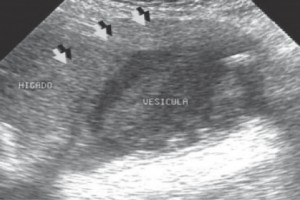

Diplomados en Ultrasonografía